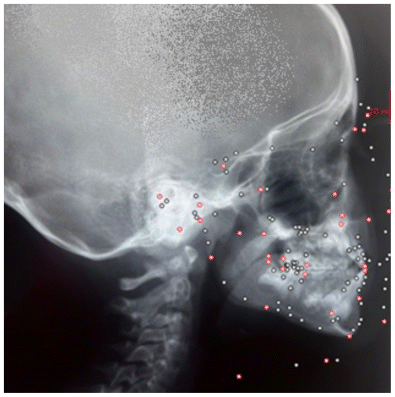

Materials and Methods: A total of 11 pediatric patients (5 boys and 6 girls) aged between 6 and 12 years were included in the study. All patients exhibited Class III malocclusion and were treated with the AMCOP® TC elastodontic appliance. The device was worn for two hours in the afternoon and overnight for an initial period of 6–8 months, followed by exclusive nighttime wear. Lateral cephalometric radiographs were taken at the start (T0) and end (T1) of the treatment. All radiographic data were evaluated using DeltaDent® software.

Lateral cephalograms were analyzed at T0 and T1 using DeltaDent® software to measure treatment outcomes.